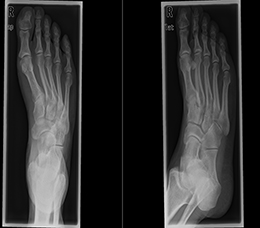

Röntgenuntersuchungen finden breite Anwendungen. Sie dienen u.a. zur Darstellung von Knochen und Gelenken nach Verletzungen, zur Beobachtung des Heilungsverlaufes nach Brüchen und Gelenkersatz, zur Beurteilung der Verschleißerscheinungen bei Arthrose, zum Nachweis von Tumoren (Mammographie), sowie zur Erfassung des Zustandes kranker Zähne. Sie werden auch zur Beurteilung der Lunge, des Bauches, zur Darstellung von Tränen- und Speicheldrüsen sowie zur Kontrolle der Nahrungspassage in der Speiseröhre und im Magen-Darmtrakt eingesetzt.